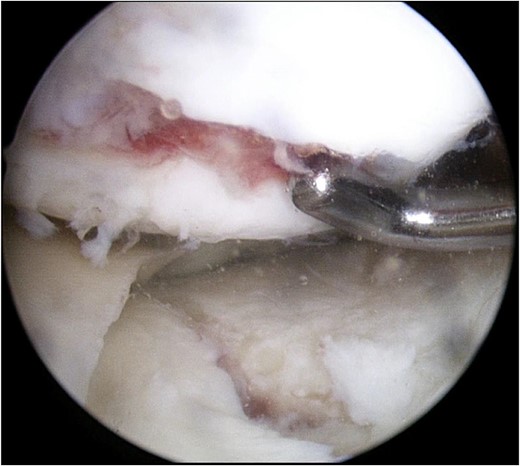

Consecutive surgeries, including internal fixation for TPF and ACI for cartilage injury, were planned. During the first surgery, the arthroscopic examination revealed ICRS grade IV cartilage injury of the medial femoral condyle and depressed medial tibial plateau (Fig. 4). The depressed medial tibial plateau was elevated and reduced. Then artificial bone chips were inserted into the defect beneath the plateau, and the fracture was fixed using the TriS Medial HTO Plate System (Olympus Terumo Biomaterials Corp., Tokyo, Japan) (Fig. 5). Finally, approximately 0.5 mg of healthy cartilage was harvested from a non-weight-bearing area of the lateral femoral condyle. The cartilage was cultured in a three-dimensional environment at the facility (Japan Tissue Engineering Co., Ltd., Gamagori, Japan) for 4 weeks. Next, open ACI was performed 4 weeks after the initial surgery, as described in a previous study [8]. The cultured cartilage was transplanted into the cartilage defect of the femur and covered by the periosteum, which was harvested from the proximal tibia [9]. The periosteum was sutured around cartilage using the 1.4 mm JuggerKnot® soft anchor system (Zimmer Biomet, Warsaw, IN, USA). Postoperative rehabilitation included partial weight bearing at 4 weeks and full weight bearing at 8 weeks. The patient was permitted to perform heavy labor and sports activities 9 months after the surgery.

Arthroscopic findings of the medial compartment of the left knee at the initial surgery. Complete cartilage loss of the femoral condyle to the subchondral area and a depressed medial tibial plateau were observed.